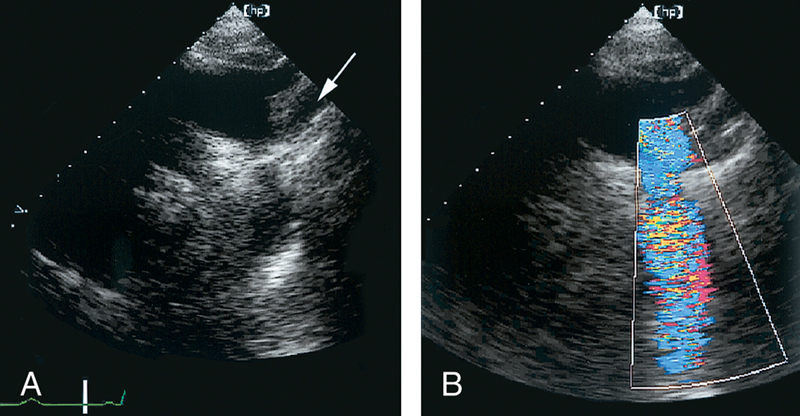

فحوصات تشخيصية لبعض امراض القلب والشرايين التاجية